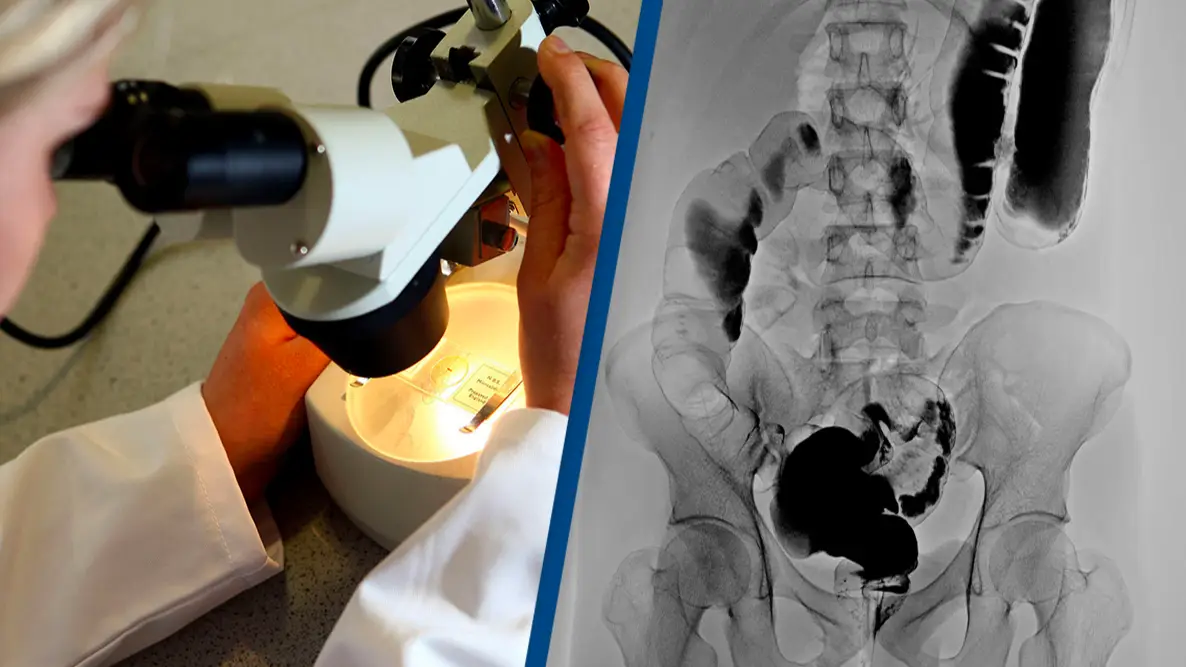

The report stated: "Regression of the patient’s metastatic lung lesions was observed on computed tomography at the first clinical follow-up 1 month after the cell infusion, with an overall objective partial response according to the Response Evaluation Criteria in Solid Tumors (RECIST), version 1.1, of 62%."

Six months after the treatment, her tumours had reduced by 72 percent.